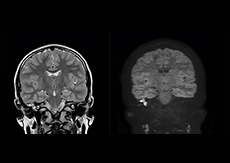

“Imaging cholesteatoma, benign tumors of the middle ear, has been a huge challenge,” says Dr. Heggelman. “We used to do CT, but then we were unsure if we were looking at an inflammation or a cholesteatoma. Also determining if residual cholesteatoma exist after surgery or visualizing recurrence used to be very difficult. Adding Diffusion TSE in our MRI protocol now effectively addresses this.” “Diffusion TSE is far less sensitive to susceptibility differences than previously used EPI sequences. We appreciate the high resolution and the robustness of the sequence. The quality is so good that our confidence has increased. Also our ENT (ear, nose, throat) physicians are excited about the high resolution, the excellent lesion delineation and the sensitivity and specificity.”

“We also love MultiVane XD for motion reduction in imaging. We find this a huge step forward. We use it in the head, and of course in the upper abdomen, and the images are outstanding most of the time. And it can be combined with dS SENSE parallel imaging for speed.” “We have compared image quality of FLAIR with MultiVane XD versus FLAIR without MultiVane XD. In 15 of the 40 patients studied, we saw motion artifacts on plain FLAIR brain images. The FLAIR images with MultiVane XD were motion-free in 39 of 40 patients and showed slight motion artifacts in only one patient.”